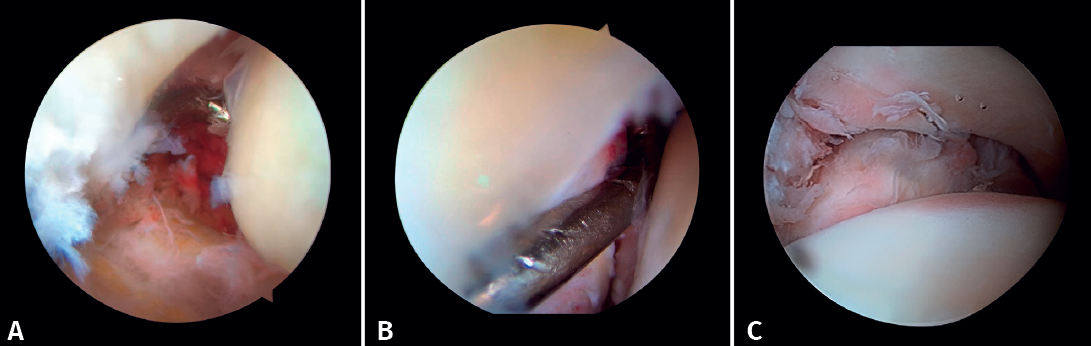

Si es posible, realizaremos la reinserción de fragmentos osteocondrales inestables (Figura 3). En las lesiones condrales donde no es posible reinsertar el fragmento, pueden emplearse técnicas de estimulación de reparación del cartílago(5,13).

Figura 3. A: cuerpos libres; B: lesión osteocondral; C: reducción de la lesión osteocondral; D: estimulación medular.